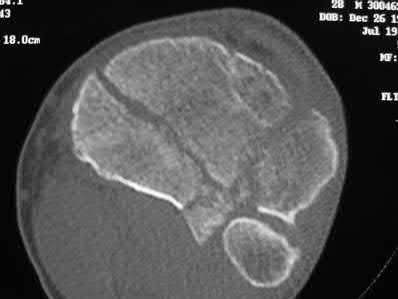

A 25-year-old female is involved in a motor vehicle collision. She presents with the isolated injury seen in Figures A through D. Her leg is swollen but her skin is intact. She has no clinical signs of compartment syndrome. Which of the following treatment options will allow for maintenance of fracture alignment and minimize the risk of soft tissue complications?

The patient presents with a closed distal third metaphyseal-diaphyseal distal tibia fracture with simple intra-articular extension. Immediate intramedullary nailing along with percutaneous fixation of the articular component provides appropriate restoration of length, rotation and alignment and minimizes the risk of wound complication.

Figures A and B demonstrate a distal third tibial shaft fracture with simple intra-articular extension. The axial and coronal CT cuts in Figures C and D further clarify the articular injury. Illustrations A and B demonstrate a comminuted distal third tibial fracture with simple intra-articular extension. Illustrations C and D are fluoroscopic images of the same injury after intramedullary nailing and percutaneous fixation of the articular component.